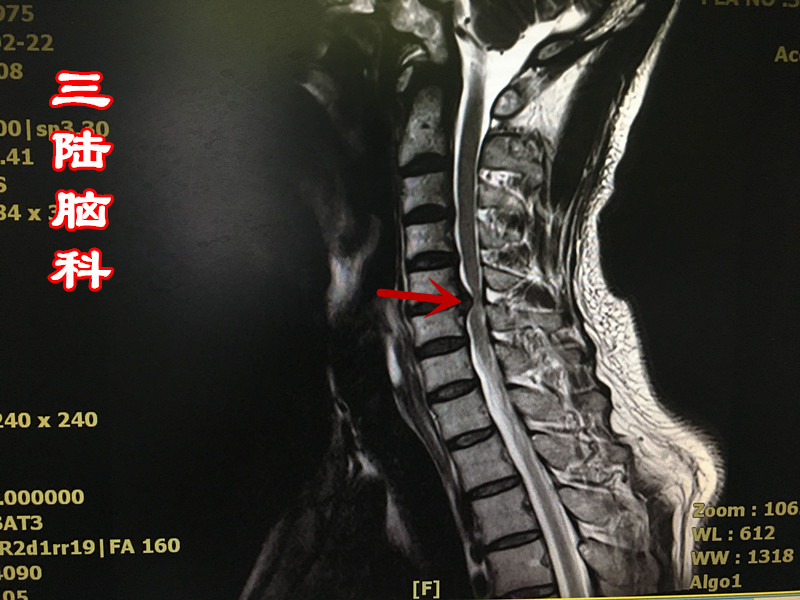

术前颈椎磁共振显示颈椎间盘多节段突出,颈髓受压呈串珠状,颈髓变性!

三陆脑科谈脑病|颈椎间盘突出患者的救助案例

会造成颈髓受压,严重造成脊髓变性,导致脊髓型颈椎病,患者会出现双